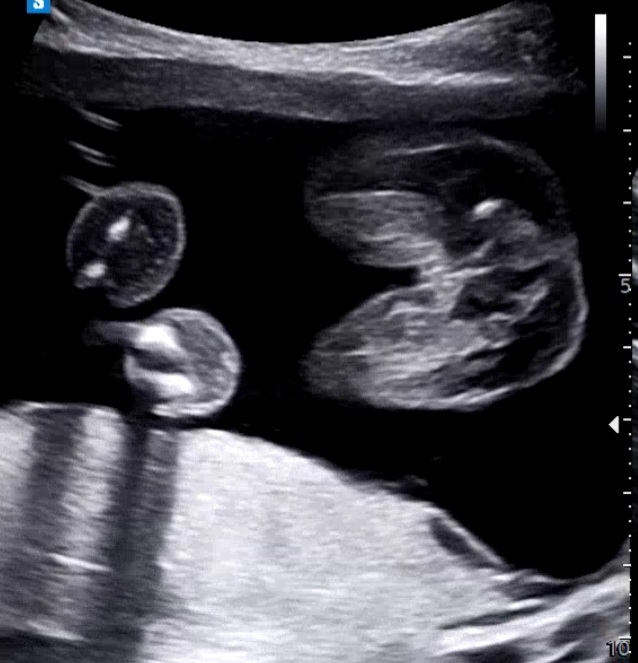

병원에서 28주 전에는 성별을 말해줄수없다고하시면서 엄마가 초음파봤을때 보이면 아들 안보이면 딸이라고 하셨어요~ 근데 저는 잘 모르겠다고했는데 선생님 왈" 안보일만했네요"라고 하셨어요 이 말이 있는데 안보였다라는건지 없으니깐 안보인다는건지 참 중의적인 표현을 해주셔서 과연 아들일까요? 딸일까요~?

올리신 사진상으로는 딸이네요. 아들은 삼각점에 빼박 총알 뿅! 하고 나와있어요ㅜ 두아들맘 인증이요ㅠㅎㅎ 근데 보통 16주면 힌트 주시는데.. 28주까지 안알려주시는건.. 좀 그렇네요

아무것도 없으니 안보일만 했다는것같아용ㅎ 너무나 딸..

딸같아요 ㅎㅎ 아들은 존재감이 확실해서^^!